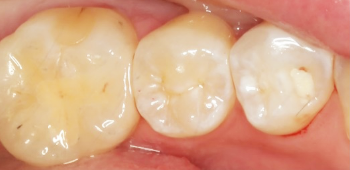

虫歯の治療も現在はセラミックの治療が最も良いとされています。

銀の詰め物と比較して『精度』が良く、再度虫歯になるリスクが低いです。

保険治療で使用されるセメントは熱によって膨張と収縮を繰り返し、長期間の使用により劣化してくることが示唆されています。

その結果内部に隙間ができ0.3㎛の大きさの細菌の侵入を許し虫歯になってしまいます。

当院のセラミック治療は適合も良く、セメントも歯と化学的に接着するものなので細菌の侵入を防ぐことが出来、さらに審美的です。

| 治療期間 | 2週間 |

|---|---|

| 費用 | セラミックインレー 6万6千円(顕微鏡治療の場合10万円) |